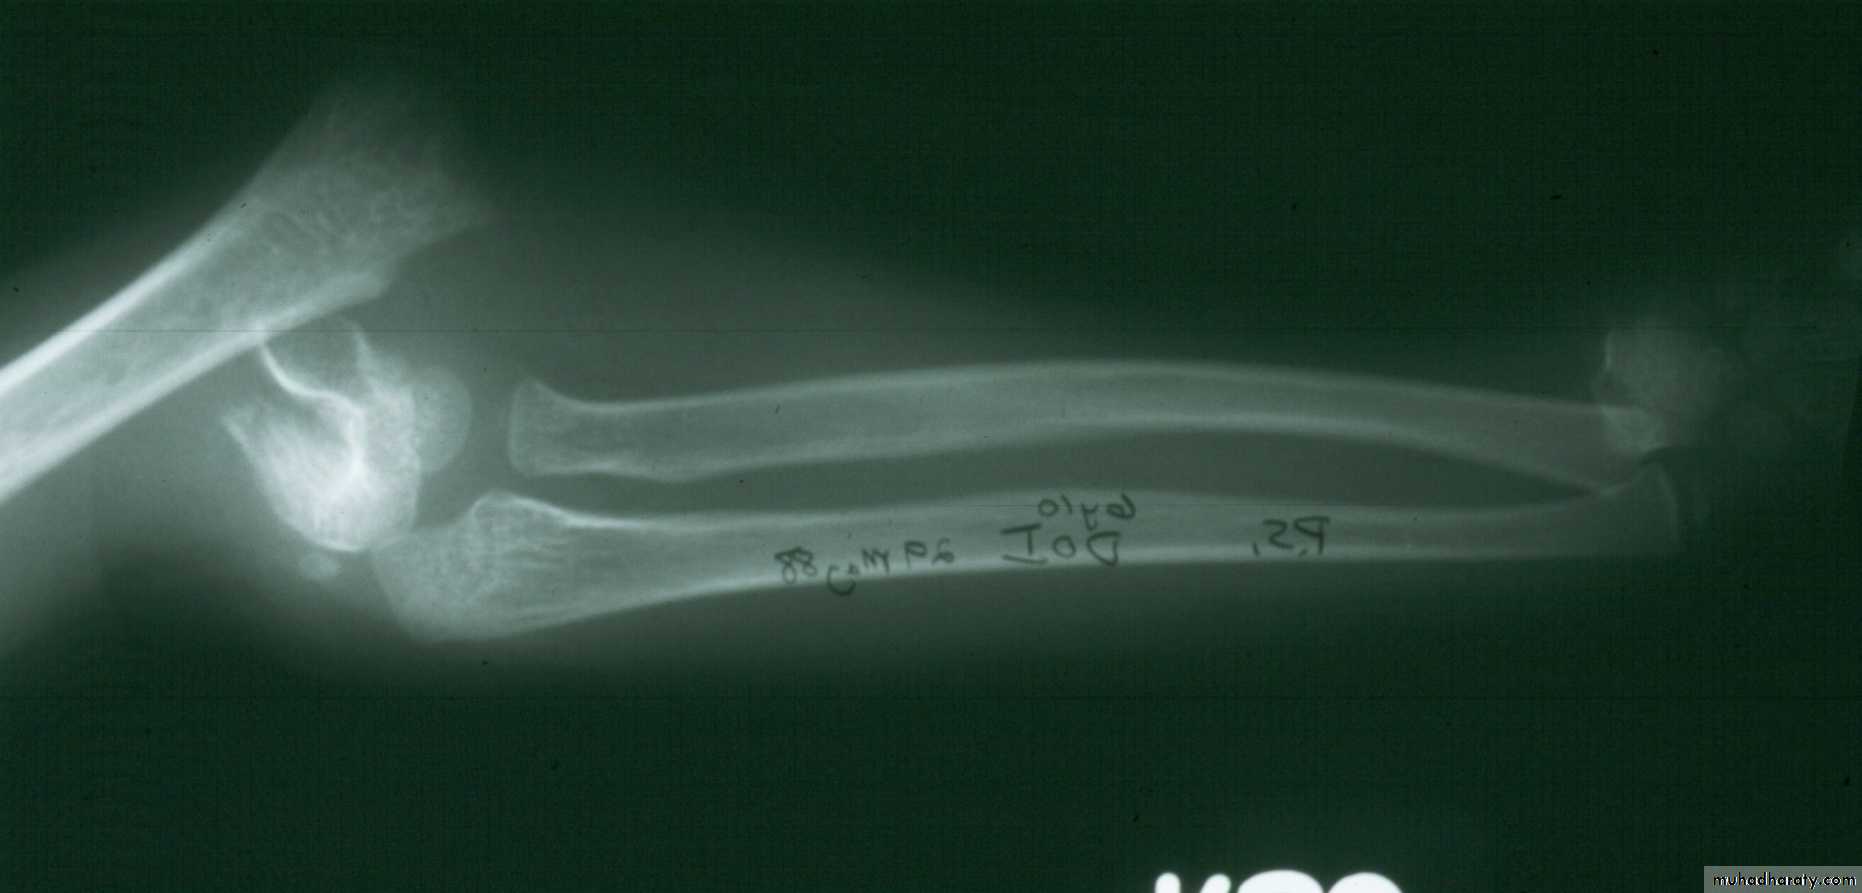

What type of supracondylar fracture

does this patient have?Flex

ionHow do the flexion patterns present?

They present

in the same manner as the extension types.Type I Flexion Injury

This classical Type III pattern

is obviously a flexion injury.With these one needs to be

prepared to do an open reduction !!

8 y.o.

Is this a simple extension

type supracondylar fracture ??

It also has

anterolatateraldisplacement !!

The distal fragment is

not flexed,but also it is not extended to any degree.

This also is a Type III Flexion Pattern.

What is differentabout this fracture?

But, if not recognized as such, it may be a problem.

This fracture was irreducible,

and required an open reduction !!!

There are some clues to these occult flexion injuries.

1. The distal fragment is not extended,

however,it may not be flexed to any degree.

It may be

rotated!!2. The distal fragment is in valgus.

3. The medial spike of the proximal fragment is usually posterior.